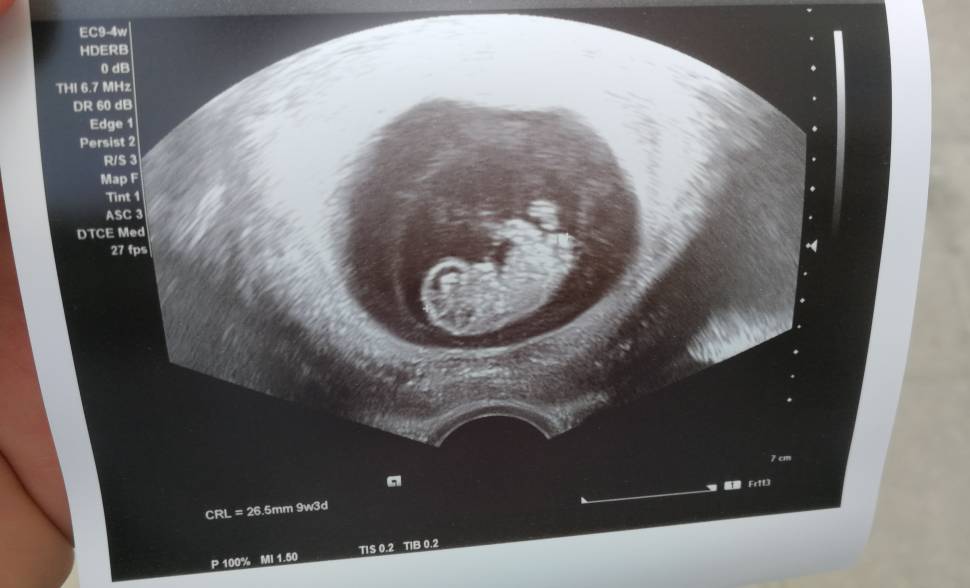

Nasze USG

Mój człowieczek malutki [emoji3590] niecałe 3cm, tętno 171. No kocham go/ją już [emoji28]

Niestety nie. Wstydnis bardzo utrudnial wszystkie pomiary. Musieliśmy zrobić przerwę w badaniu i po pół godziny drugie podejście bo nie mógł lekarz uchwycić ani przeziernosci karkowej, ani kości nosowej nie było widać, ale w końcu się udało. A nóżki zacisniete całe badanie :)